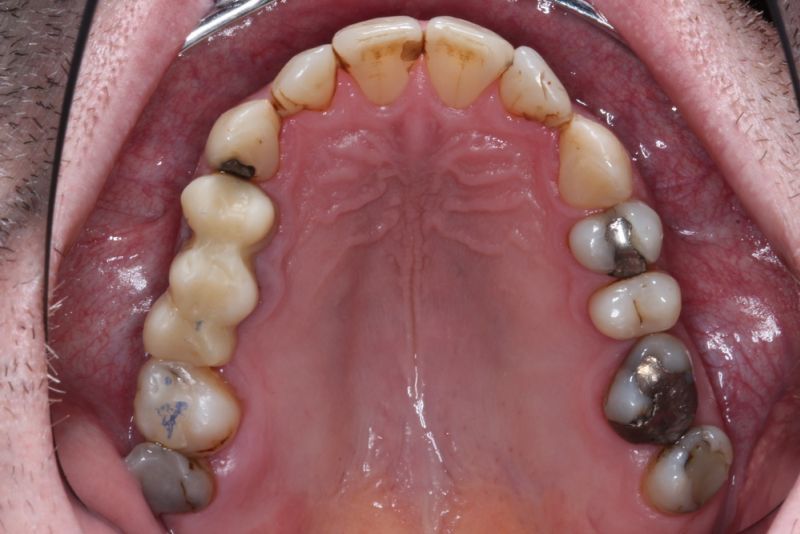

Erkennbar ist die massive Abweichung der habituellen Bisslage von der neuromuskulär zentrierten Bisslage.